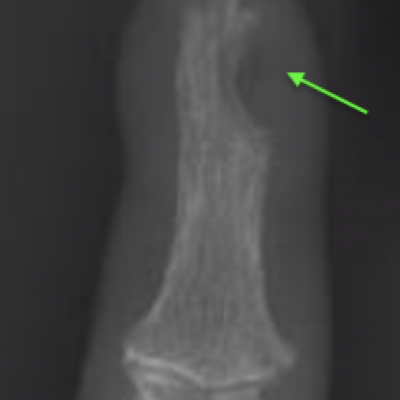

This is a rare benign (non-cancerous) growth often under the fingernail or fingertip pulp and can involve bone.

It commonly causes severe pain in the fingertip in cold environments and extreme pain and sensitivity to touch. X-Ray and MRI can be useful tests in confirming the diagnosis.